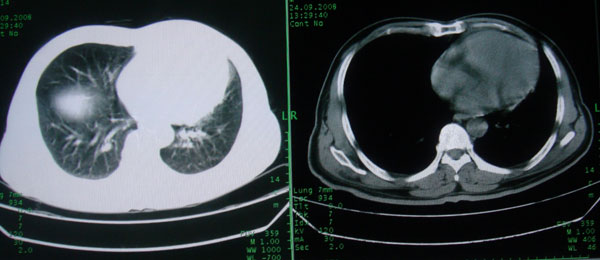

患者男性58岁因二周前起咳嗽,今天胸片示左上肺占位性病变行ct检查,无发热,无咯血痰.

左肺上叶病灶,实变但见含气支气管、空洞但未见壁内结节及积液;

考虑:①感染性病变(包括特殊感染型肺tb)

②肿瘤性病变(考虑患者年龄比较大的关系/所以不排除)

初学者。。。左肺空洞性病变,并可见阻塞性肺不张改变,鉴于患者为老年男性,且临床症状仅有咳嗽,全身中毒症状不明显,所以我首先考虑为左肺癌性空洞并左侧肺门淋巴结转移伴左肺阻塞性肺不张。结核性空洞放于第二位考虑,可以进行相关实验室检查。希望能有病理结果,谢谢!!!!!

左肺上叶实变影,内见支气管充气征及空洞影,病人年龄较大,无发热及结核中毒症状,心影左移,未见纵隔淋巴结肿大;不知实验室检查结果如何?有否嗜酸细胞增多,有没有进行治疗?就目前资料首先考虑1.感染性病变,2.慢性嗜酸性肺炎?可结合实验室检查并短期治疗复查,肺癌不能排除。